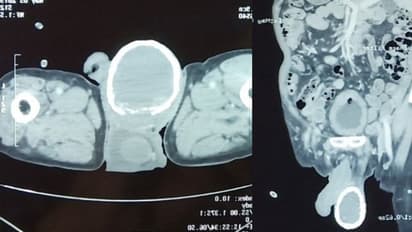

തുടര്ന്ന് നടത്തിയ സി ടി സ്കാനില് വൃഷണത്തില് വെള്ളം നിറഞ്ഞ 'hydrocele' എന്ന അപൂര്വ അവസ്ഥയാണ് രോഗിക്ക് എന്ന് സ്ഥിരീകരിച്ചു. കൂടാതെ വൃഷണത്തില് കാത്സ്യം അടിഞ്ഞ് ഒരു മുട്ടത്തോടു പോലെ രൂപപ്പെട്ടിരുന്നു. Calcification എന്നാണു ഇതിനെ പറയുന്നത്.

സാധാരണ ശരീരത്തില് കാത്സ്യം എല്ലുകളില് നിന്ന് രക്തത്തിലൂടെ ശരീരത്തിന്റെ എല്ലാ ഭാഗങ്ങളിലും എത്താറുണ്ട്. എന്നാല് ഇത് ഒരിടത്തു മാത്രം അടിഞ്ഞു കൂടുമ്പോള് ആണ് പ്രശ്നം. സയന്സ് അലേര്ട്ടാണ് വാര്ത്ത റിപ്പോര്ട്ട് ചെയ്തിരിക്കുന്നത്.